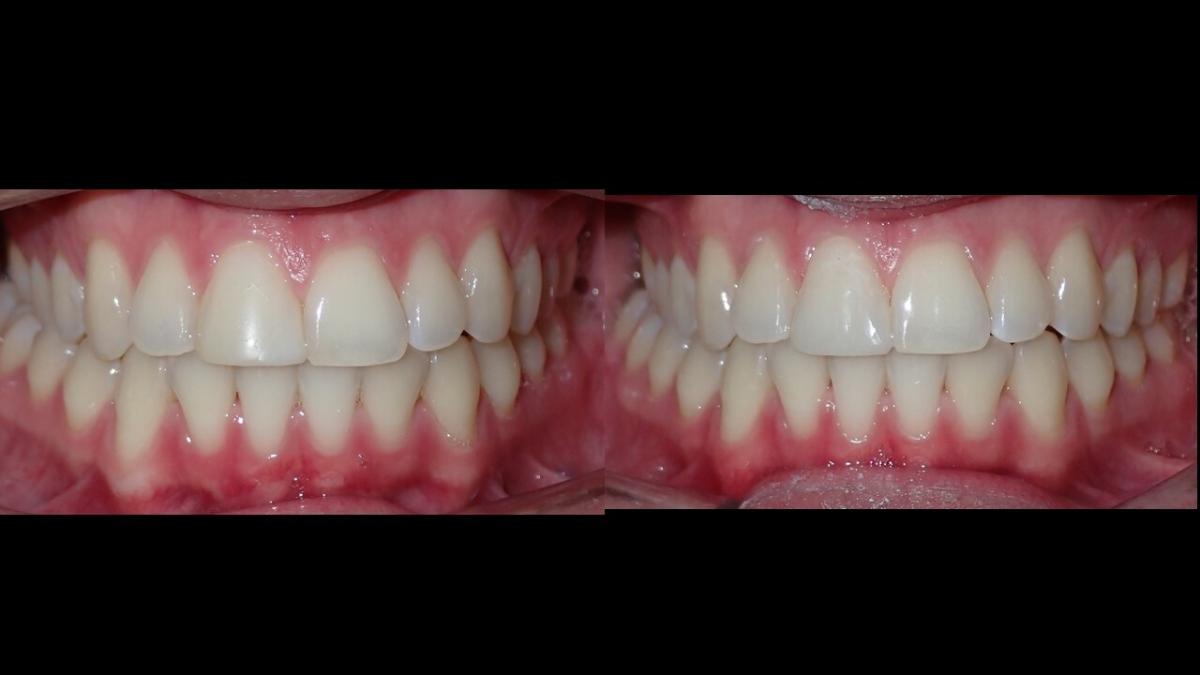

large-Resultados sin que se note ortodoncia

large-Resultados con balance